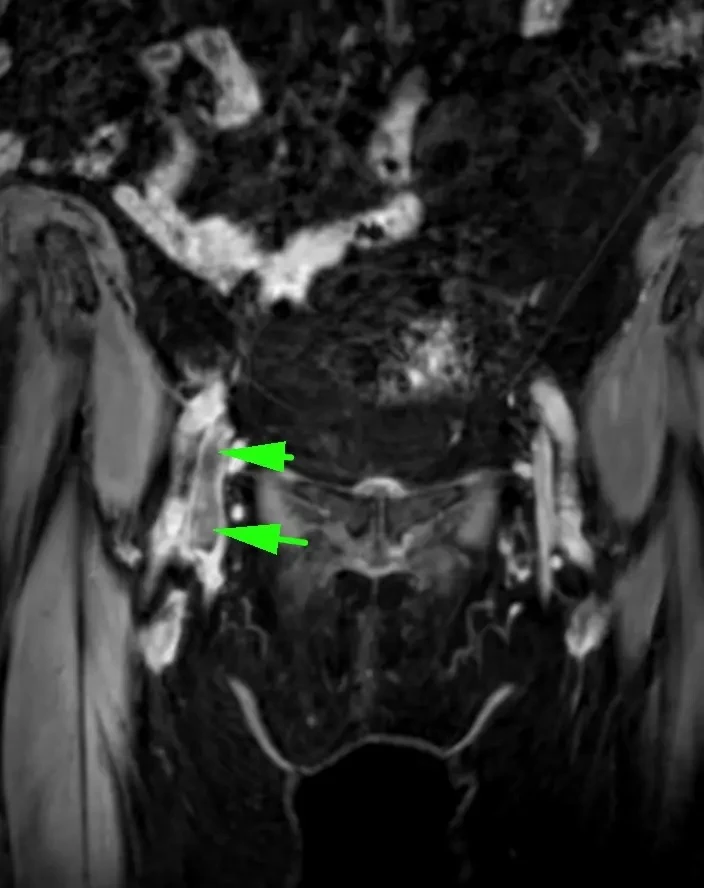

Семь менингиом и метастаз (рака молочной железы).

Четко видно, как по строению отличаются доброкачественные опухоли от злокачественных.

Первые яркие, четкие, шаровидные/полушаровидные, видно прикрепление широким основанием к костям, даже у самой мелкой.

А метастаз неровный, неяркий, нечеткий, неровный, из-за некроза, инвазии в мозг и перифокального отека.

Смотрим и запоминаем!